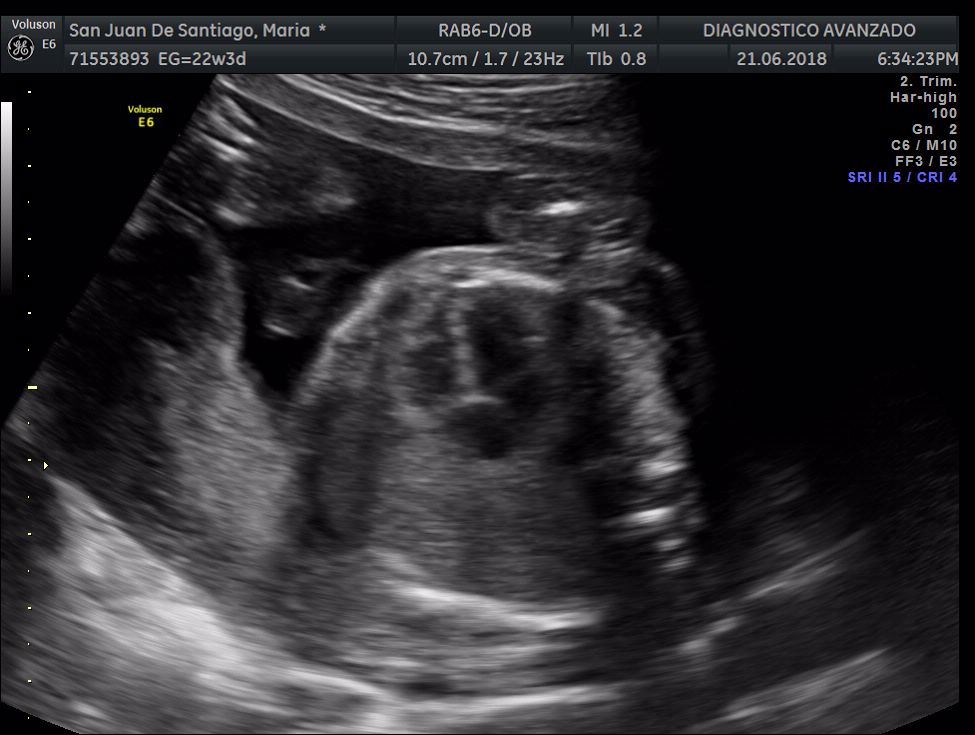

¡Hola a todos! Hoy hemos ido a hacer la tradicional ecografía 3D de la niña, os dejamos todo el material (aunque es un poco demasiado).